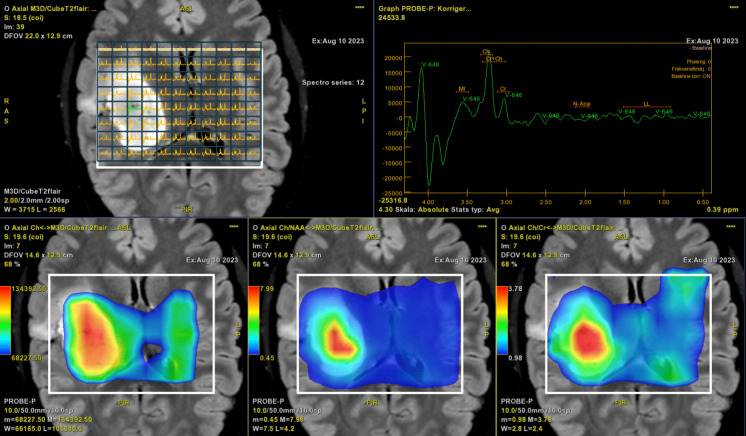

Abstract Image